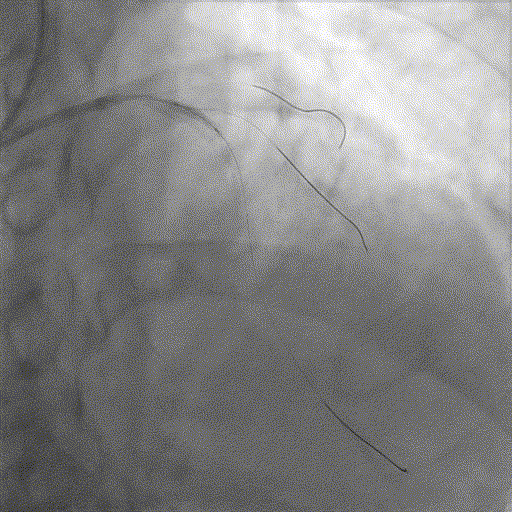

LAD处理:

球囊预扩

用预扩球囊扩张LAD病变,支架无法通过。为了解血管病变分布情况及钙化程度,遂启用IVUS检查。

术前腔内影像学IVUS指导

IVUS提示LAD近中段钙化病变,中段可见360°环形钙化。

冲击波球囊治疗

3.0x12@4atm 冠脉血管内冲击波导管顺利推送至前降支近端,但无法通过成角钙化处,故于血管近端就地进行10个周期治疗,复查造影见近端狭窄明显减轻;再次选择2.5x12@4atm冠脉血管内冲击波导管推送至成角钙化处,逐步掘进扩张病变并给予冲击波治疗,最终顺利通过成角钙化处,并于前降支中段再次进行10个周期的冲击波治疗。

支架植入并后扩

于LAD近中段串联植入两枚药物洗脱支架,经非顺应性球囊后扩张支架,复查造影及IVUS提示支架膨胀完全,贴壁良好,无夹层撕裂。